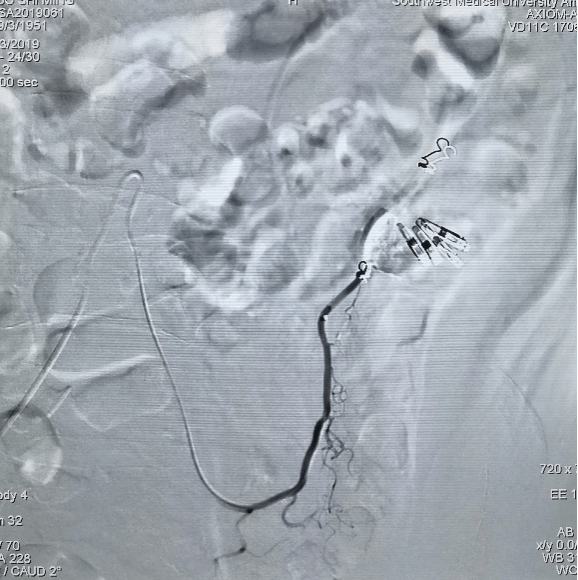

手术中过程图:

TIPS技术: